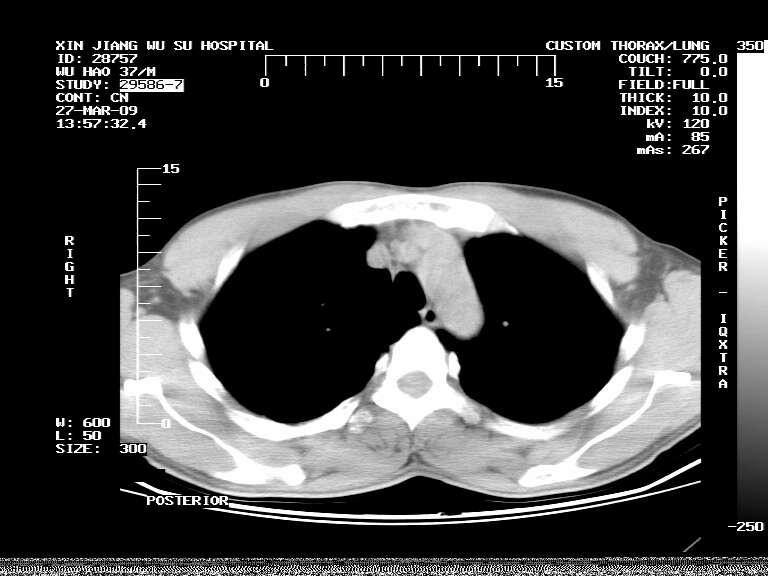

男,37岁,体检胸透发现阴影。

患者体检发现 无症状 左肺下叶占位,边缘模糊,可见血管聚束、分叶、胸膜牵拉,增强呈不均匀性强化。 首先考虑左肺下叶周围型肺癌,建议穿刺活检。

左肺下叶见一结节病变,边缘欠清不光滑,与胸膜粘连且胸膜局限性增厚,注药后呈环形强化,动脉期壁呈明显点环状强化,静脉期壁强化减低,中心密度低无强化,灶周无明显的卫星灶和水肿区(晕征)---考虑周围性肺癌,不除外感染性病变,建议穿刺活检。

左肺下叶软组织病灶,密度较高,内见点状钙化,其周围见子灶,邻近胸膜扁平样增厚.c+病灶强化明显,中心强化弱.诊断:左肺下叶结核瘤.

周围有卫星灶,胸膜反应不明显,病灶中心有坏死。建议先抗结核治疗后,短期复查

左肺下叶大片实变影,内靠胸膜见不规则更高密度结节灶,边缘强化,相邻胸膜增厚,胸膜下脂肪线存在。考虑炎症,结核可能。